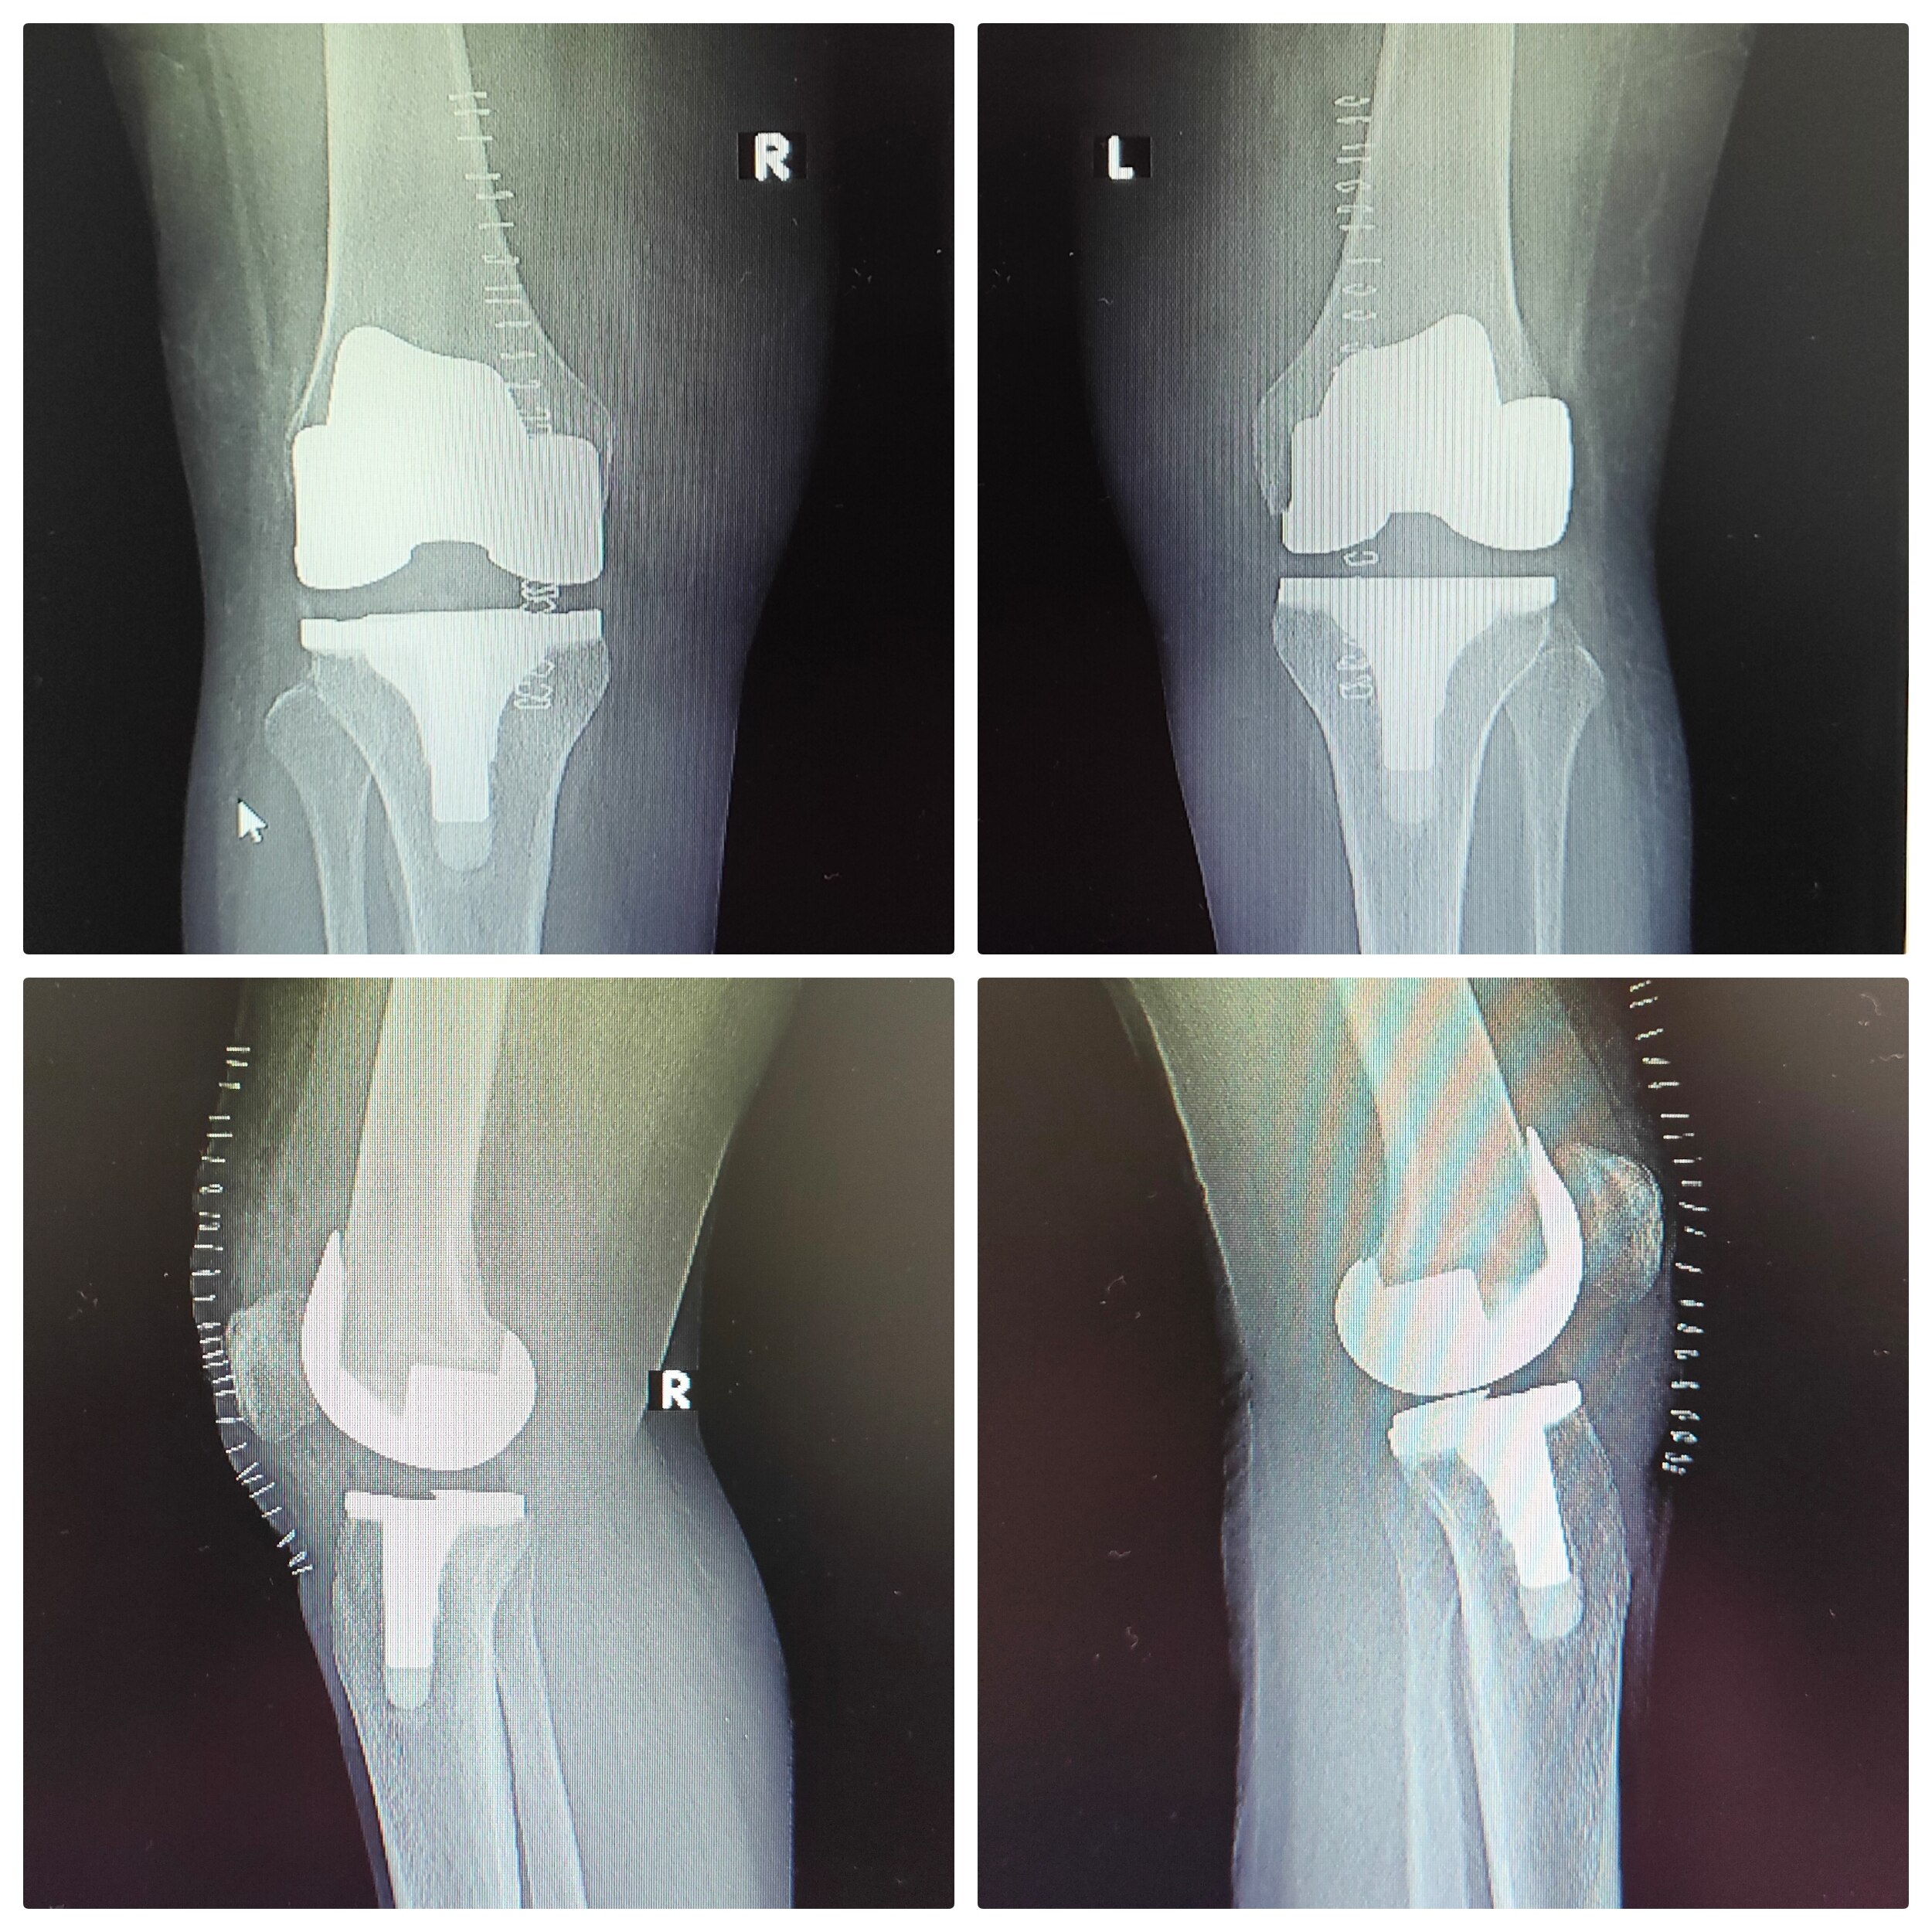

Welcome to the world of orthopedic excellence, where your health and well-being are our utmost priorities. Dr. Chetan Singh , an accomplished orthopedic surgeon, has been a dedicated practitioner in the vibrant city of Bhopal for the past 8 years. His unwavering commitment to providing exceptional orthopedic care has earned him a reputation as a trusted healthcare professional in the region. Meet Dr. Chetan Singh is a highly skilled orthopedic surgeon who has dedicated his career to improving the lives of patients suffering from orthopedic conditions. His educational journey began with the completion of an MBBS degree from Devi Ahilya Vishwa Vidyalaya, Indore, M.P. in 2015, where he laid the strong foundation for his medical expertise. Driven by his passion for orthopedics and a desire to offer the best care possible, Dr.Chetan Singh continued his educational journey. In 2019, he successfully achieved a Master of Surgery (MS) in Orthopedics from Madhya Pradesh Medical Science University, Jabalpur. This rigorous training equipped him with the knowledge, skills, and advanced techniques necessary to diagnose, treat, and manage a wide spectrum of orthopedic conditions.